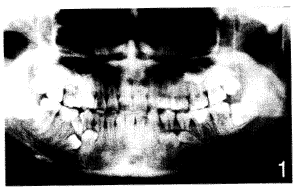

华西口腔学杂志990437 多生牙多见于上中切牙之间,亦可见于下颌双尖牙区或上磨牙区。尚未查见双侧上下颌骨多发性埋伏多生牙并先天缺牙的报道。现将作者收诊一例报告如下。

全口曲面断层片(图1)显示:

根尖下方两个埋伏多生牙,形态为双尖牙,单根,髓腔粗大,根尖孔已闭。

根尖已部分吸收。

根尖下方两个埋伏多生牙,形态不规则,介于双尖牙与磨牙形之间,髓腔粗大,根尖孔未闭。

根方可见各有一埋伏多生牙,根尖喇叭口状。

根方未见有

埋伏阻生。追问病史,自述既往无拔牙史。家族其他成员牙列整齐,无类似病史。诊断:多发性埋伏多生牙并先天缺牙。